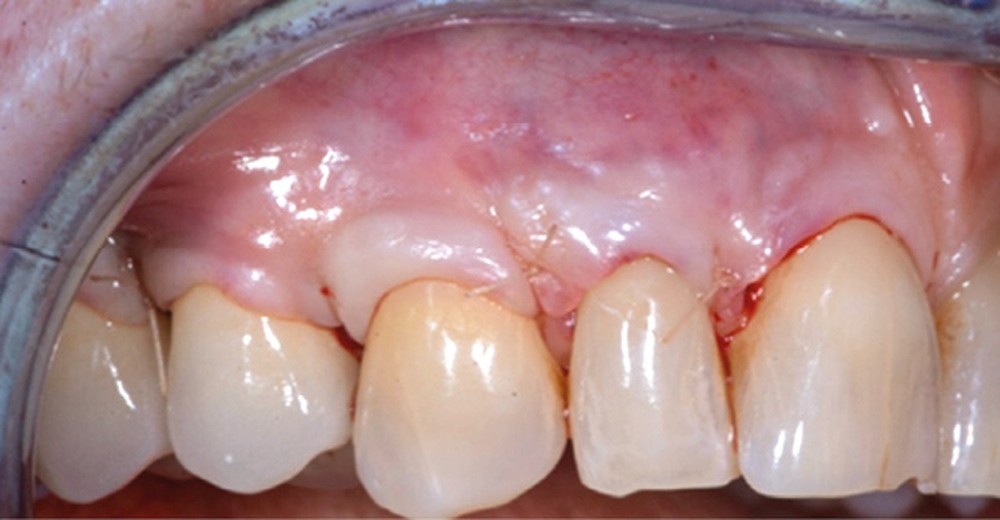

Le lambeau est ensuite décollé grâce à la méthode partielle-totale-partielle (« Split-Full-Split »). Les papilles chirurgicales sont décollées en épaisseur partielle afin d’obtenir un lit receveur et de stabiliser la position du lambeau au moment des sutures. Le lambeau est levé en pleine épaisseur jusqu’à la ligne de jonction muco-gingivale afin d’emporter le périoste, qui permet la vascularisation du lambeau. Enfin, dans un objectif de gain de laxité, le lambeau sera disséqué en demi-épaisseur dans la muqueuse alvéolaire. Cette dissection se fait en deux plans : un plan profond et un plan superficiel parallèle au lambeau muqueux. Le but est de permettre de repositionner le lambeau avec un minimum de tension.

Cette technique, sans greffon de conjonctif associé, permet un taux de recouvrement complet de 80 %. La préservation de l’épaisseur du lambeau et la présence du périoste semble jouer un rôle fondamental dans l’obtention du recouvrement complet.